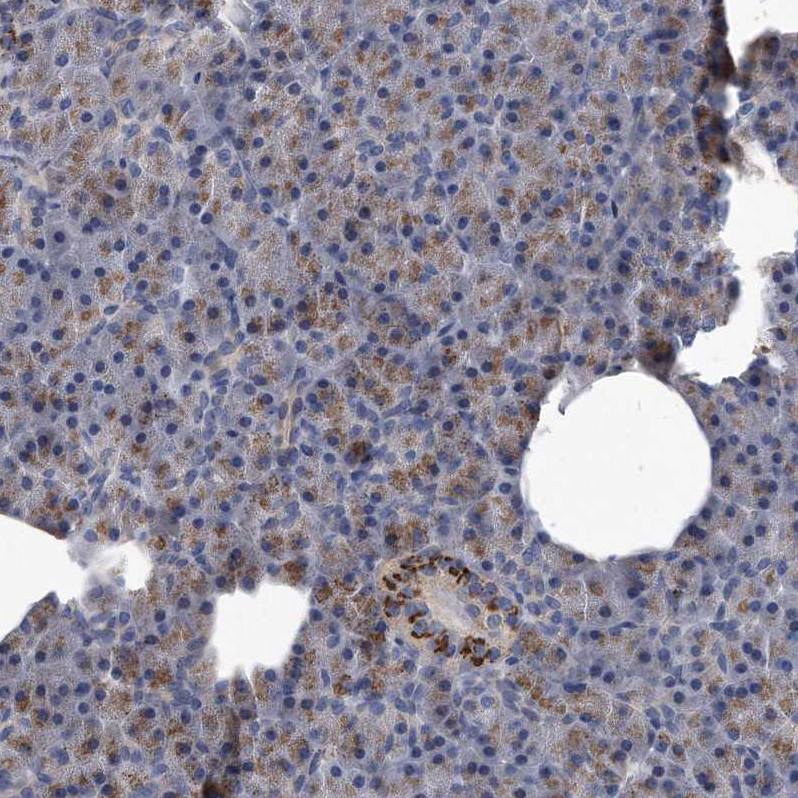

Immunohistochemical staining of human pancreas shows moderate granular cytoplasmic positivity in islets of Langerhans.